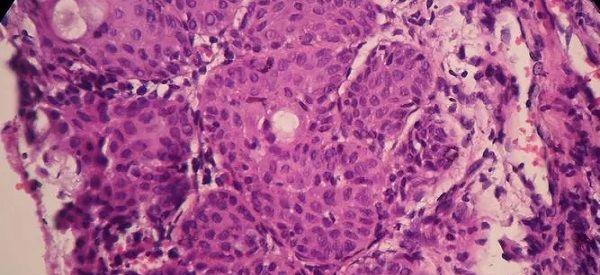

子宫内膜变薄,女性要省视自己的身体情况,看是否为以下原因造成:

1、做人工流产手术,导致损伤到子宫内膜的基底层;

2、患有子宫内膜结核疾病,也会引起子宫内膜变薄;

3、药物所致,尤其是一些放疗药物的影响;

4、女性患有内分泌失调方面的疾病。

临床上发现子宫内膜厚度主要是由雌激素水平决定的,与黄体酮并没有关系,女性身体内的雌激素是帮助子宫内膜增长的重要物质,而孕激素是增殖期的子宫内膜转化为分泌期的子宫内膜,女性子宫内膜是胚胎着床的重要场所,如果要想试管移植后胚胎能成功着床,子宫内膜还还需要满足以下条件: